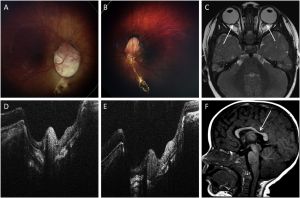

Fundoscopic examination of patients with Aicardi Syndrome shows pathognomonic multiple chorioretinal lacunae that are typically bilateral, round, non-elevated, and without vessels crossing over their surface. Thinning of the choroid and sclera and degeneration of the overlying rods and cones causes a yellow-white to pinkish appearance. Variable border pigmentation can occur due to photoreceptor folds at the edges of the lesions that are lined with pigmented and nonpigmented epithelial cells. [18][3][15][16][19] The overlying retina is intact, but typically has an abnormal appearance on histology. Lacunae vary in size from 1/10th to 3 disc diameters and are clustered around the optic nerve head and posterior pole, decreasing in size towards the periphery. Lesion size and number are characteristically consistent over time, but some show increased or fading pigmentation.[3][15][16][20][8][19]

Additional ocular abnormalities include colobomas of the optic nerve and microphthalmos in approximately 44% and 20% of patients, respectively. Optic nerve anomalies, pupillary membrane remnants, iris colobomas, choroidal colobomas, morning glory discs, retinal detachment, altered foveal development, nystagmus, sixth cranial nerve palsy, glial tissue extending from the optic disc, hyperplastic primary vitreous, choroidal neovascularization, retinopathy of prematurity, severe congenital ptosis, late onset retinoblastoma, and aniridia have also been described in Aicardi Syndrome, albeit less frequently.[15][16][8][19]